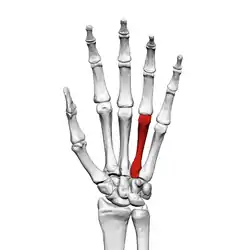

Fourth metacarpal bone

The fourth metacarpal bone (metacarpal bone of the ring finger) is shorter and smaller than the third.

The base is small and quadrilateral; its superior surface presents two facets, a large one medially for articulation with the hamate, and a small one laterally for the capitate.

On the radial side are two oval facets, for articulation with the third metacarpal; and on the ulnar side a single concave facet, for the fifth metacarpal.